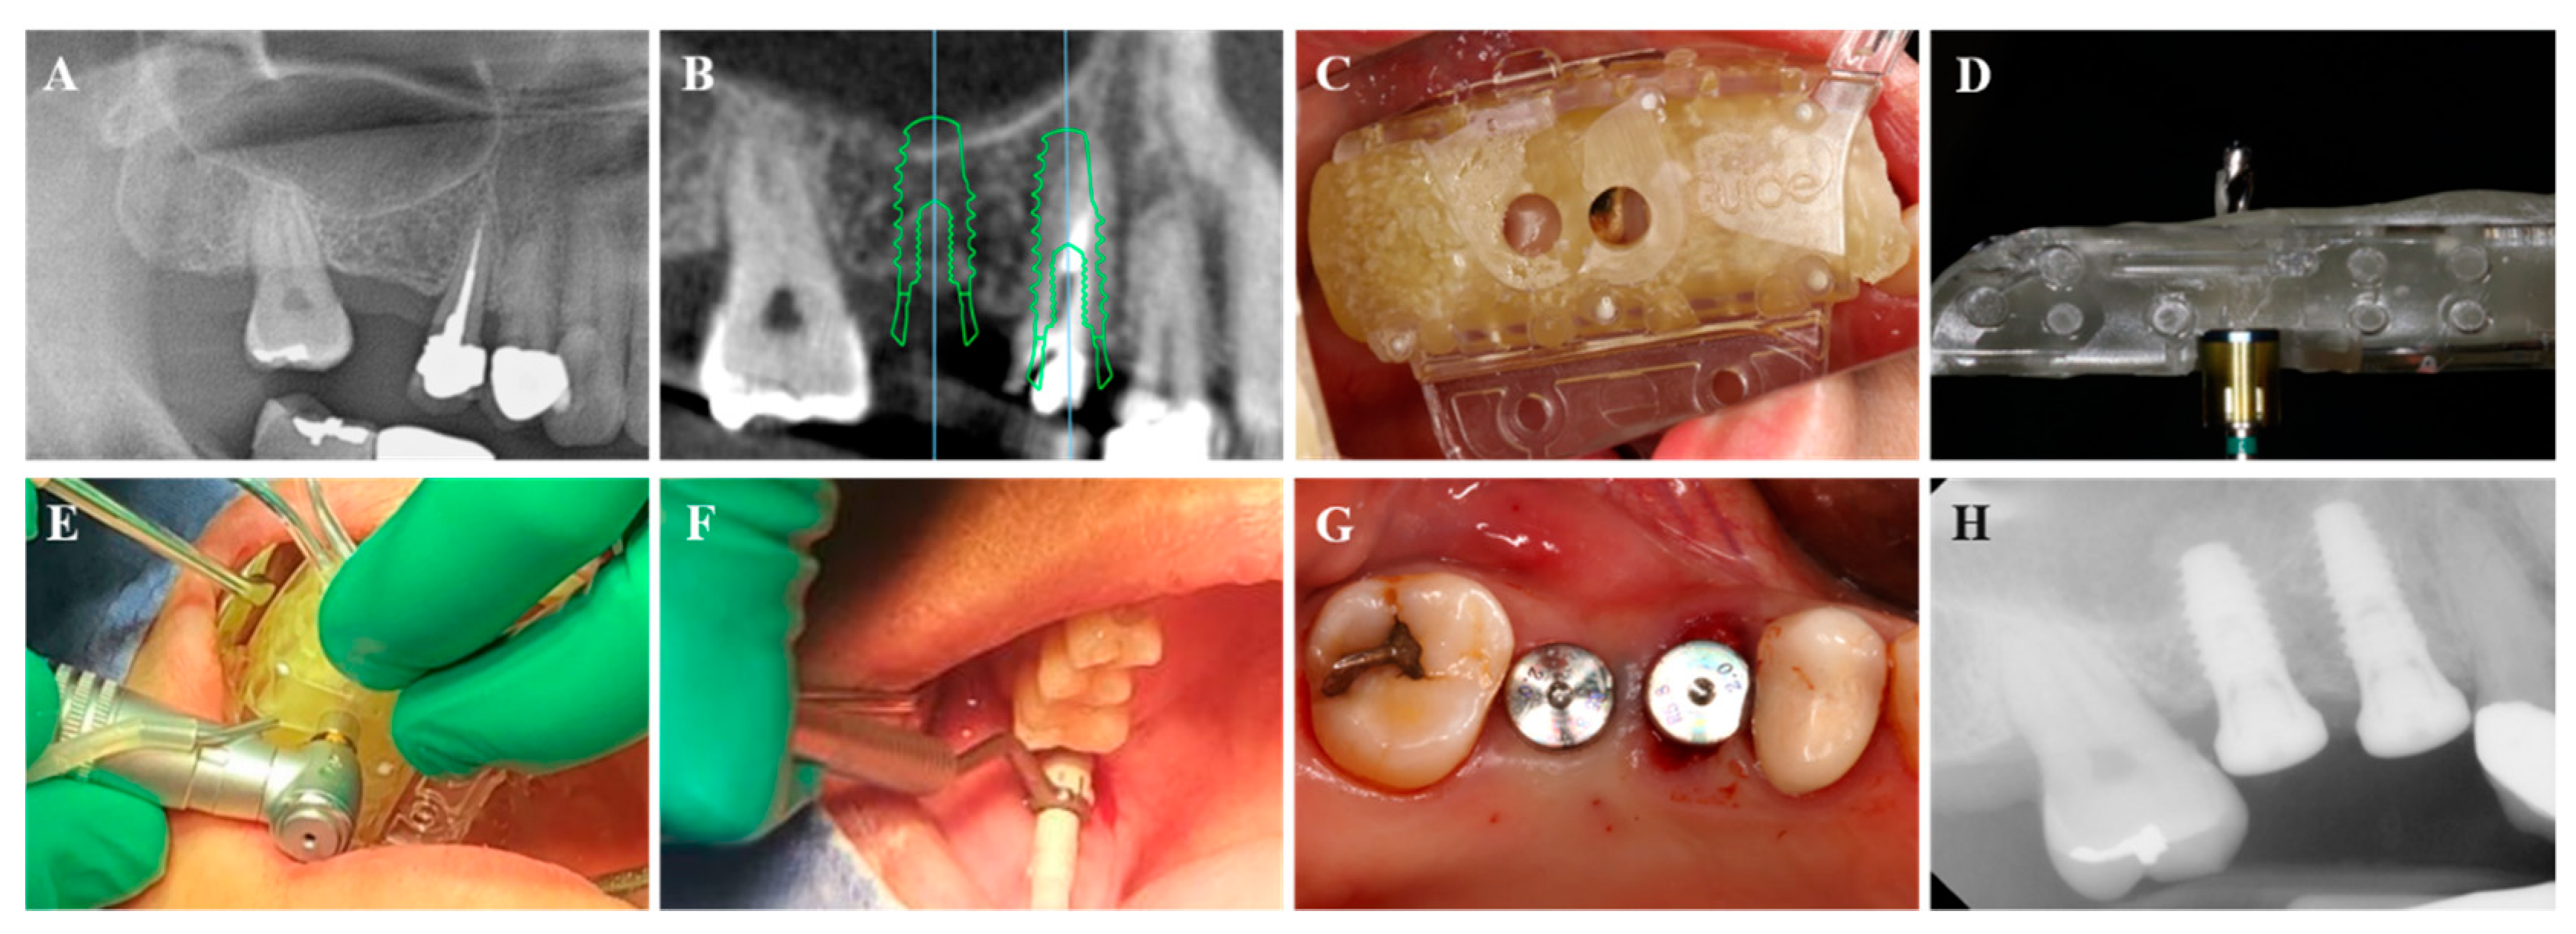

2.2. Treatment Protocol

2.2.1. VARO Guide Fabrication

2.2.2. Fully-Guided Implant Placement with Flapless Crestal Sinus Augmentation